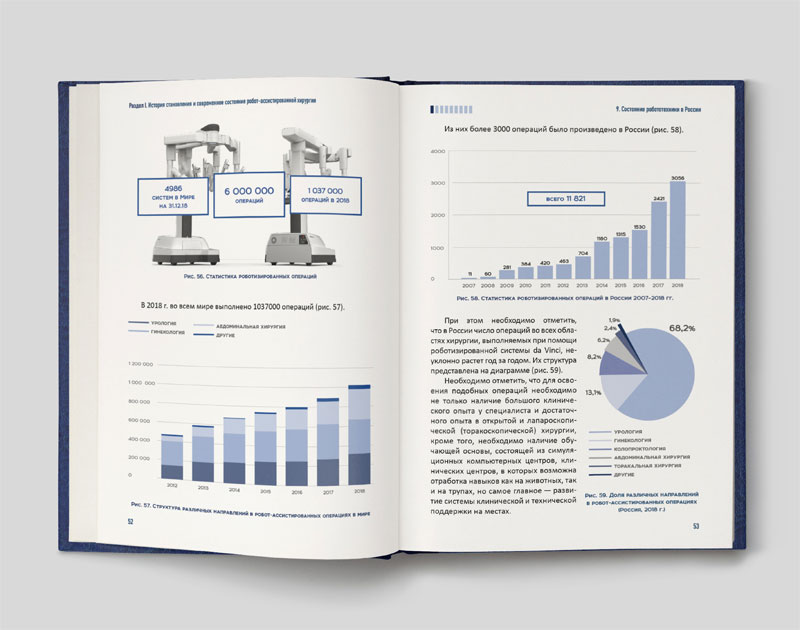

Впервые в России выполнена робот-ассистированная операция с использованием системы «Da Vinci» на грудном отделе позвоночника по поводу оссифицированной грыжи межпозвонкового диска с компрессией спинного мозга